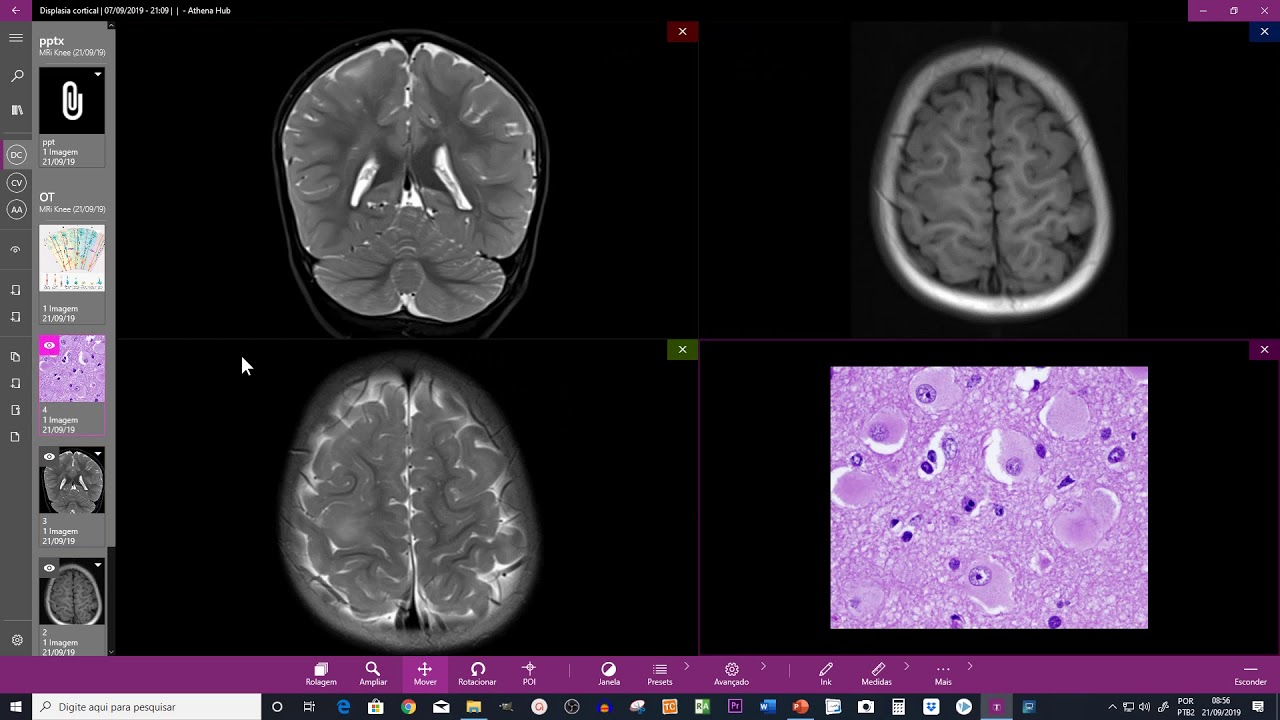

Webinar Imágenes en Epilepsia: Displasias Corticales Focales

DISPLASIA CORTICAL FOCAL TIPO II B